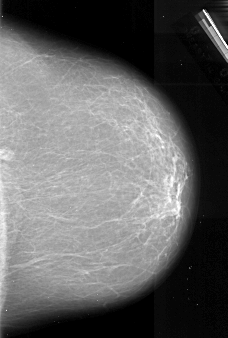

A_1011_1.RIGHT_CC

RIGHT_MLO LINES 6766 PIXELS_PER_LINE 4486 BITS_PER_PIXEL 16 RESOLUTION 42 NON_OVERLAY